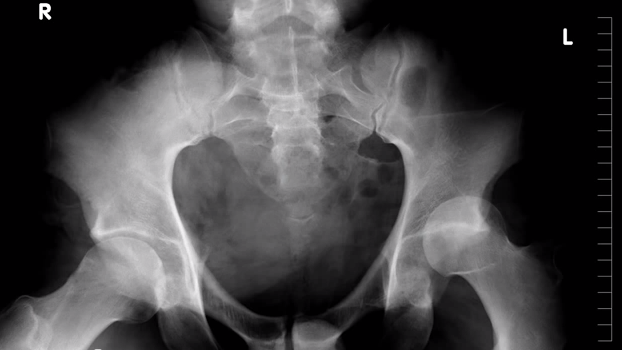

"The 2013 season has been my most challenging year to date. I dislocated my hip in January, making me sit out the rest of the year. My first and last time Ill be out for the season. This video touches lightly on what it takes to recover from a serious injury and return to skiing.